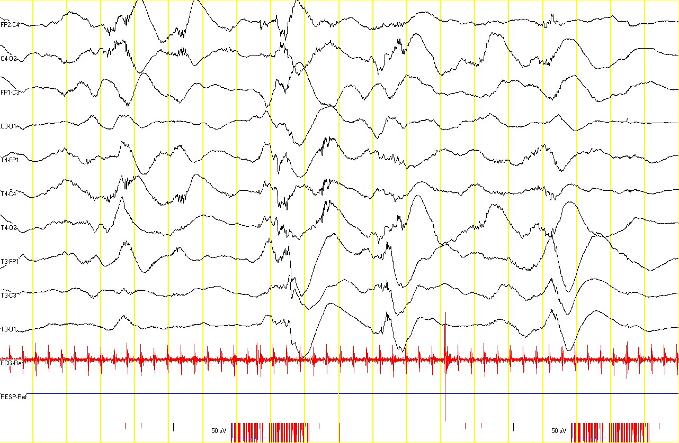

Images d'EEGs

EEG du mois